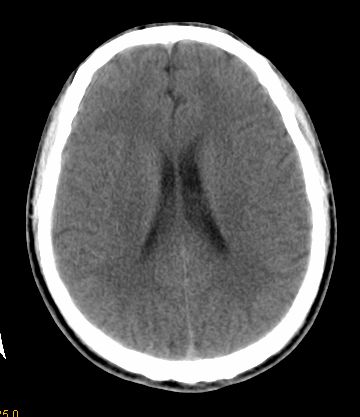

男 42岁 头痛20天

左顶叶见片状低密度影,边界不清,内见斑片状等密度影。考虑转移性肿瘤可能性大,建议ct增强或mr增强扫描。建议胸部检查,排除肺部病变。

左顶叶见片状低密度影,内似见结节状略高密度影,建议增强扫描。

左侧顶叶低密度灶,性质待定;建议行ct增强扫描或mri检查。

左顶叶见片状低密度影,边界不清,内见斑片状等密度影。考虑转移性肿瘤可能性大,建议ct增强或mr增强扫描。建议胸部检查,排除肺部周围型腺癌。